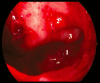

Endonasal endoscopic sinus surgery is the standard procedure for surgery of most paranasal sinus diseases. Appropriate frame conditions provided, the respective procedures are safe and successful. These prerequisites encompass appropriate technical equipment, anatomical oriented surgical technique, proper patient selection, and individually adapted extent of surgery. The range of endonasal sinus operations has dramatically increased during the last 20 years and reaches from partial uncinectomy to pansinus surgery with extended surgery of the frontal (Draf type III), maxillary (grade 3-4, medial maxillectomy, prelacrimal approach) and sphenoid sinus. In addition there are operations outside and beyond the paranasal sinuses. The development of surgical technique is still constantly evolving. This article gives a comprehensive review on the most recent state of the art in endoscopic sinus surgery according to the literature with the following aspects: principles and fundamentals, surgical techniques, indications, outcome, postoperative care, nasal packing and stents, technical equipment.